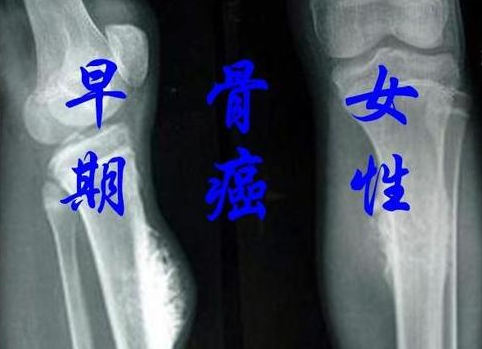

醫生提示:身體若是出現這3大癥狀,或是骨癌的早期表現,需警惕在我們這個注重健康的年代,骨癌這個名詞可能還是顯得有些遙遠和陌生。醫生們卻在提醒著我們,當身體出現某些特定的癥...